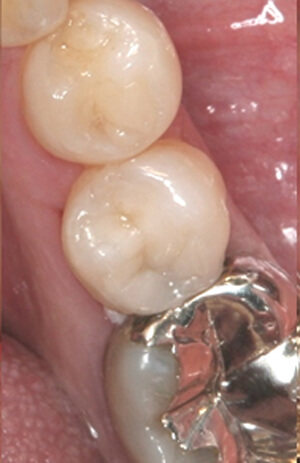

ダイレクトボンディング症例3

詰め物と虫歯

術前

奥歯の詰め物と虫歯が気になるためダイレクトボンディングを希望されました

ダイレクトボンディング 治療後

術後